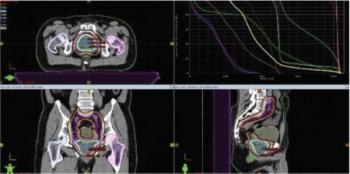

This review summarizes the current evidence supporting the use of SBRT as treatment for inoperable renal cell carcinoma, as well as provides recommendations for patient selection and reviews the technical aspects of treatment and the expected toxicities.